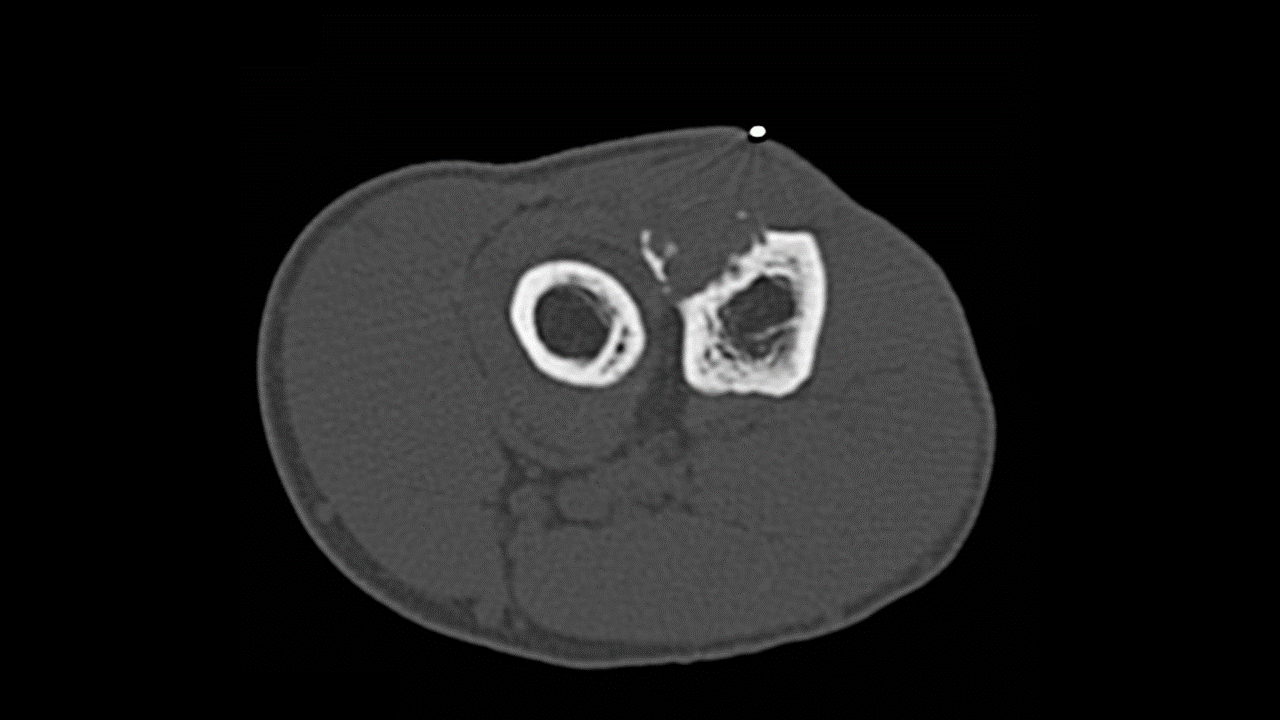

Фиброма кт